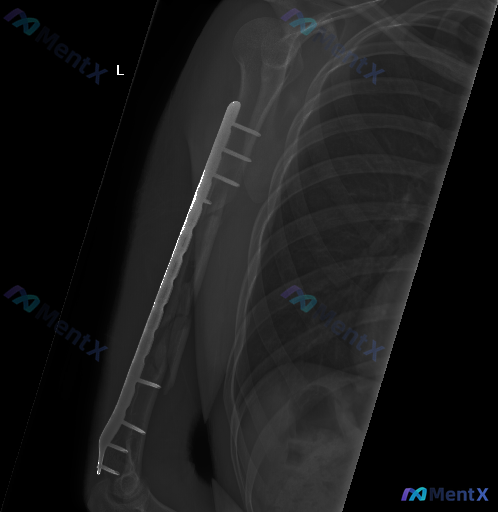

整理到一例左肱骨骨折内固定术后的复查影像资料,先把关键信息列出来,大家帮忙看看这种情况更往哪边考虑: 病例背景 左肱骨干骨折内固定术后复查(具体术后时间未明确说明)。 影像表现(左上臂+胸部X光) 1. 内固定情况:左肱骨外侧可见锁定加压接骨板及多枚螺钉固定,钢板、螺钉在位,未见明显松动、退出或断裂...

整理到一份左肱骨干骨折内固定术后的影像资料,大家可以先看一下关键表现: 基本背景:左肱骨干骨折术后复查 影像核心表现: - 肱骨外侧可见锁定加压钢板及多枚螺钉固定 - 钢板中段下方骨折区域,皮质不连续,断端存在分离及错位 - 断端周围有模糊、密度增高的骨痂形成迹象,但部分区域断端间隙仍可见,骨质连接...